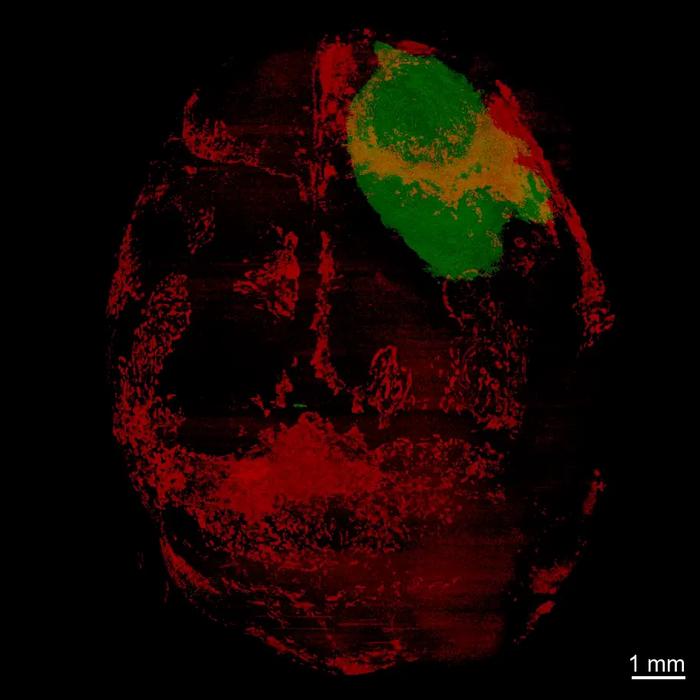

This 3D image shows the brain and skull of a glioblastoma mouse model. The green area is the tumor; the red areas are where bone-eating osteoclast cells have accumulated in the skull.

Dr. Masaru Ishii established the mouse model. Dr. Behnan established the tumor and acquired the image in Einstein's Neural Cell Engineering and Imaging Core, and the video was generated by study co-author Nathaniel Killian of the department of neurosurgery.

Credit: Albert Einstein College of Medicine